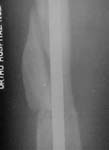

Subject: Femoral fracture with a rotated wedge

A male 19 years old admitted to us after a car accident (was inside) with this femoral fracture (see attachment). As you can see, there is a rotated fragment. The question is whether closed nailing "as is" and early knee function is enough for the case, or open reduction of the fragment should be performed?